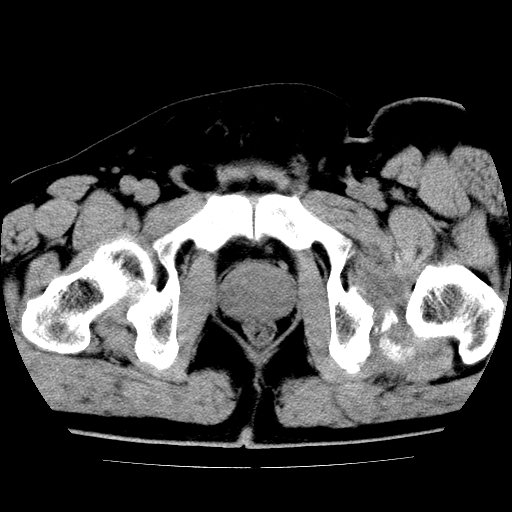

标题: CT21643:男,42岁,车祸伤后左髋关节疼痛剧烈1小时。 [打印本页]

男,42岁,车祸伤后左髋关节疼痛剧烈1小时。

左髋关节脱位并髋臼骨折,左髋关节积血。

左髋关节后脱位并髋臼骨折,左髋关节积血

左髋关节后脱位,大小转子皮质撕脱骨折,关节腔“脂血症”,左侧盆底少量积血,左侧髋臼邻关节囊肿。

左髋关节后脱位并髋臼骨折、股骨头前方骨折,左髋关节积血 。

左髋关节(股骨头)后脱位,并髋臼及股骨头骨折,左髋关节积血。

左髋关节后脱位并髋臼后缘骨折、股骨头前方骨折,左髋关节积血 。我遇到过一例。